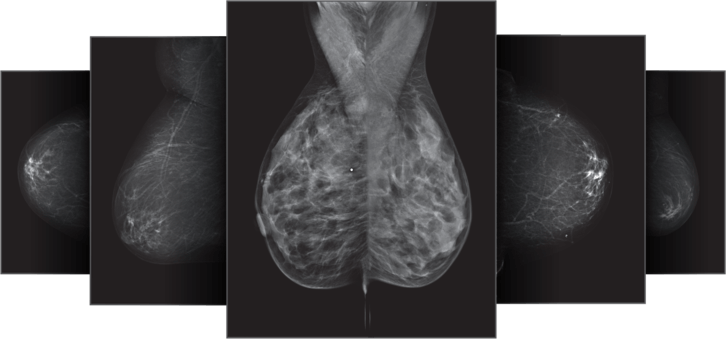

Densitas intelliMammo tackles the most pressing challenges facing breast cancer screening today.

Fully automated, on-demand, actionable information for every mammogram.

Densitas intelliMammo provides the tools to deliver personalized measures of breast density, breast cancer risk, and clinical image quality that can be used to develop unbiased, tailored screening protocols for every woman every time she has a mammogram.